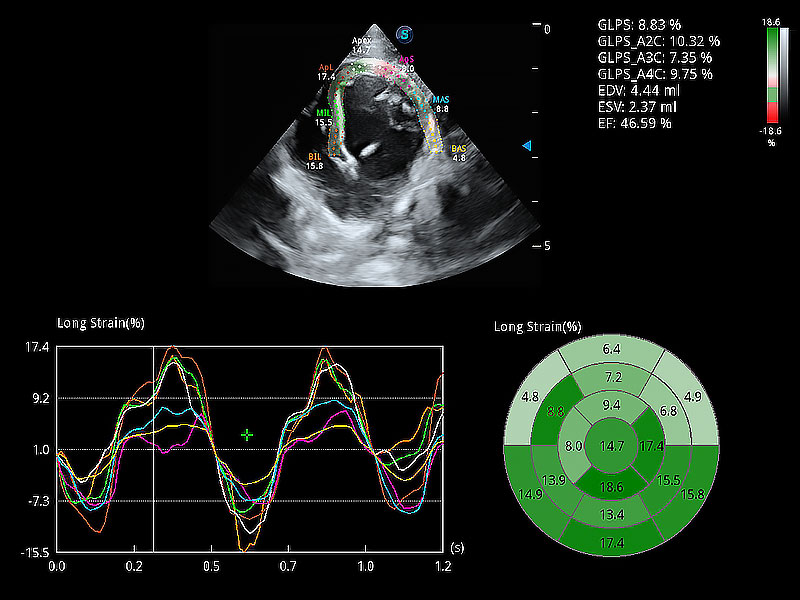

通過心肌識別技術(shù)與二維斑點(diǎn)追蹤技術(shù)相結(jié)合,對心臟的超聲圖像進(jìn)行量化分析。計算心肌17個節(jié)段的應(yīng)變、應(yīng)變率、速度、位移等,并通過牛眼圖的形式進(jìn)行呈現(xiàn)。